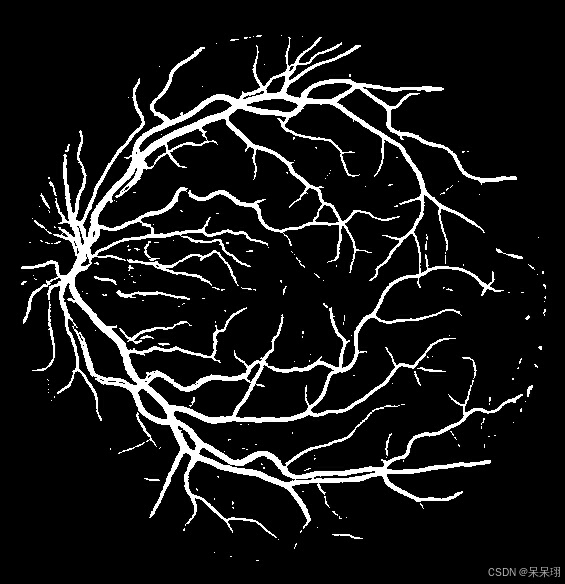

*/3.4 数据后处理

根据自己的后处理修改

ncnn::Mat out_flattened = out.reshape(out.w * out.h * out.c);

float* output_data = (float*)out_flattened.data;

cv::Mat result_img = cv::Mat::zeros(roi_img.rows, roi_img.cols, CV_8UC1);

int index = 0;

for (int row = 0; row < roi_img.rows; row++) {

for (int col = 0; col < roi_img.cols; col++) {

float channel_1 = *(output_data + index);

float channel_2 = *(output_data + index + roi_img.rows * roi_img.cols);

uchar roi_pixel = roi_img.at<uchar>(row, col);

// 如果第一个通道值小于第二个通道值,并且 ROI 像素不是黑色

if (channel_1 < channel_2 && roi_pixel != 0) {

result_img.at<uchar>(row, col) = 255; // 设置为白色

} else {

result_img.at<uchar>(row, col) = 0; // 设置为黑色

}

index++;

}

}4.完整代码和推理结果

// 保存结果图像

cv::imwrite("result.jpg", result_img);